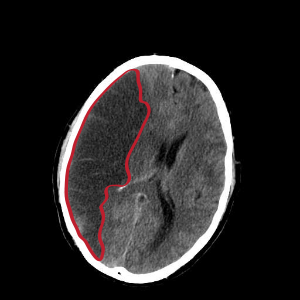

뇌경색은 혈관이 좁아지거나 막히면서 발생하는 뇌의 손상입니다. 이는 주로 혈전이나 색전으로 인해 발생하며, 그로 인해 뇌의 특정 부분에 oxygen과 영양소가 공급되지 않게 됩니다. 이 상태가 지속되면 뇌세포는 영구적으로 손상을 입거나 죽게 됩니다.

뇌경색에는 두 가지 주요 유형이 있습니다. 첫 번째는 허혈성 뇌경색으로, 대개 혈전이 혈관을 막아 발생합니다. 두 번째는 출혈성 뇌경색으로, 뇌혈관이 파열되거나 약해져 출혈이 발생하는 것입니다. 본 포스팅에서는 주로 허혈성 뇌경색의 초기 증상에 대해 설명드리겠습니다.